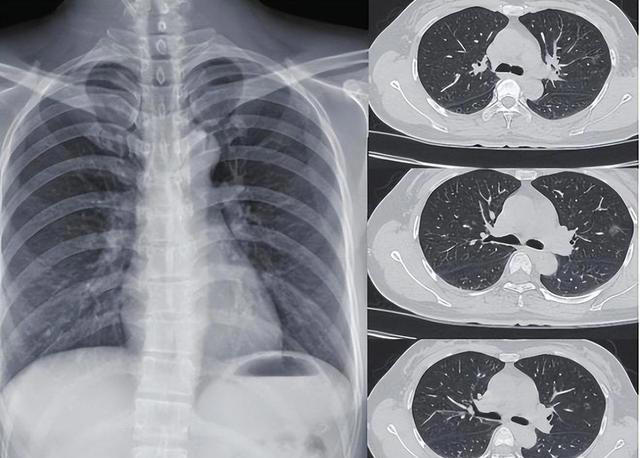

肺结节这个词现在出现频率挺高的,但它本身只是一个影像学描述,意思是肺里出现了一个圆形或类圆形的密度增高影,不等于就是癌。

结节分很多种,磨玻璃样结节、混合密度结节、纯实性结节,三者的处理逻辑和风险程度差别很大,不能一刀切地看待。

医生真正担心的,是实性结节,而且是直径达到8毫米或以上的。为什么8毫米是个分水岭?有数据支撑的。

国内外多项肺结节随访研究的数据均显示,直径不足6毫米的实性肺结节,恶性概率低于1%,几乎可以按年度随访观察。

直径在6到8毫米之间的,恶性率上升到约1.5%至6%;而一旦超过8毫米,恶性率会跳升至15%到25%,部分高危人群的比例还会更高。《中国肺癌筛查与早诊早治指南》中也明确将8毫米实性结节列为需要积极干预的阈值。